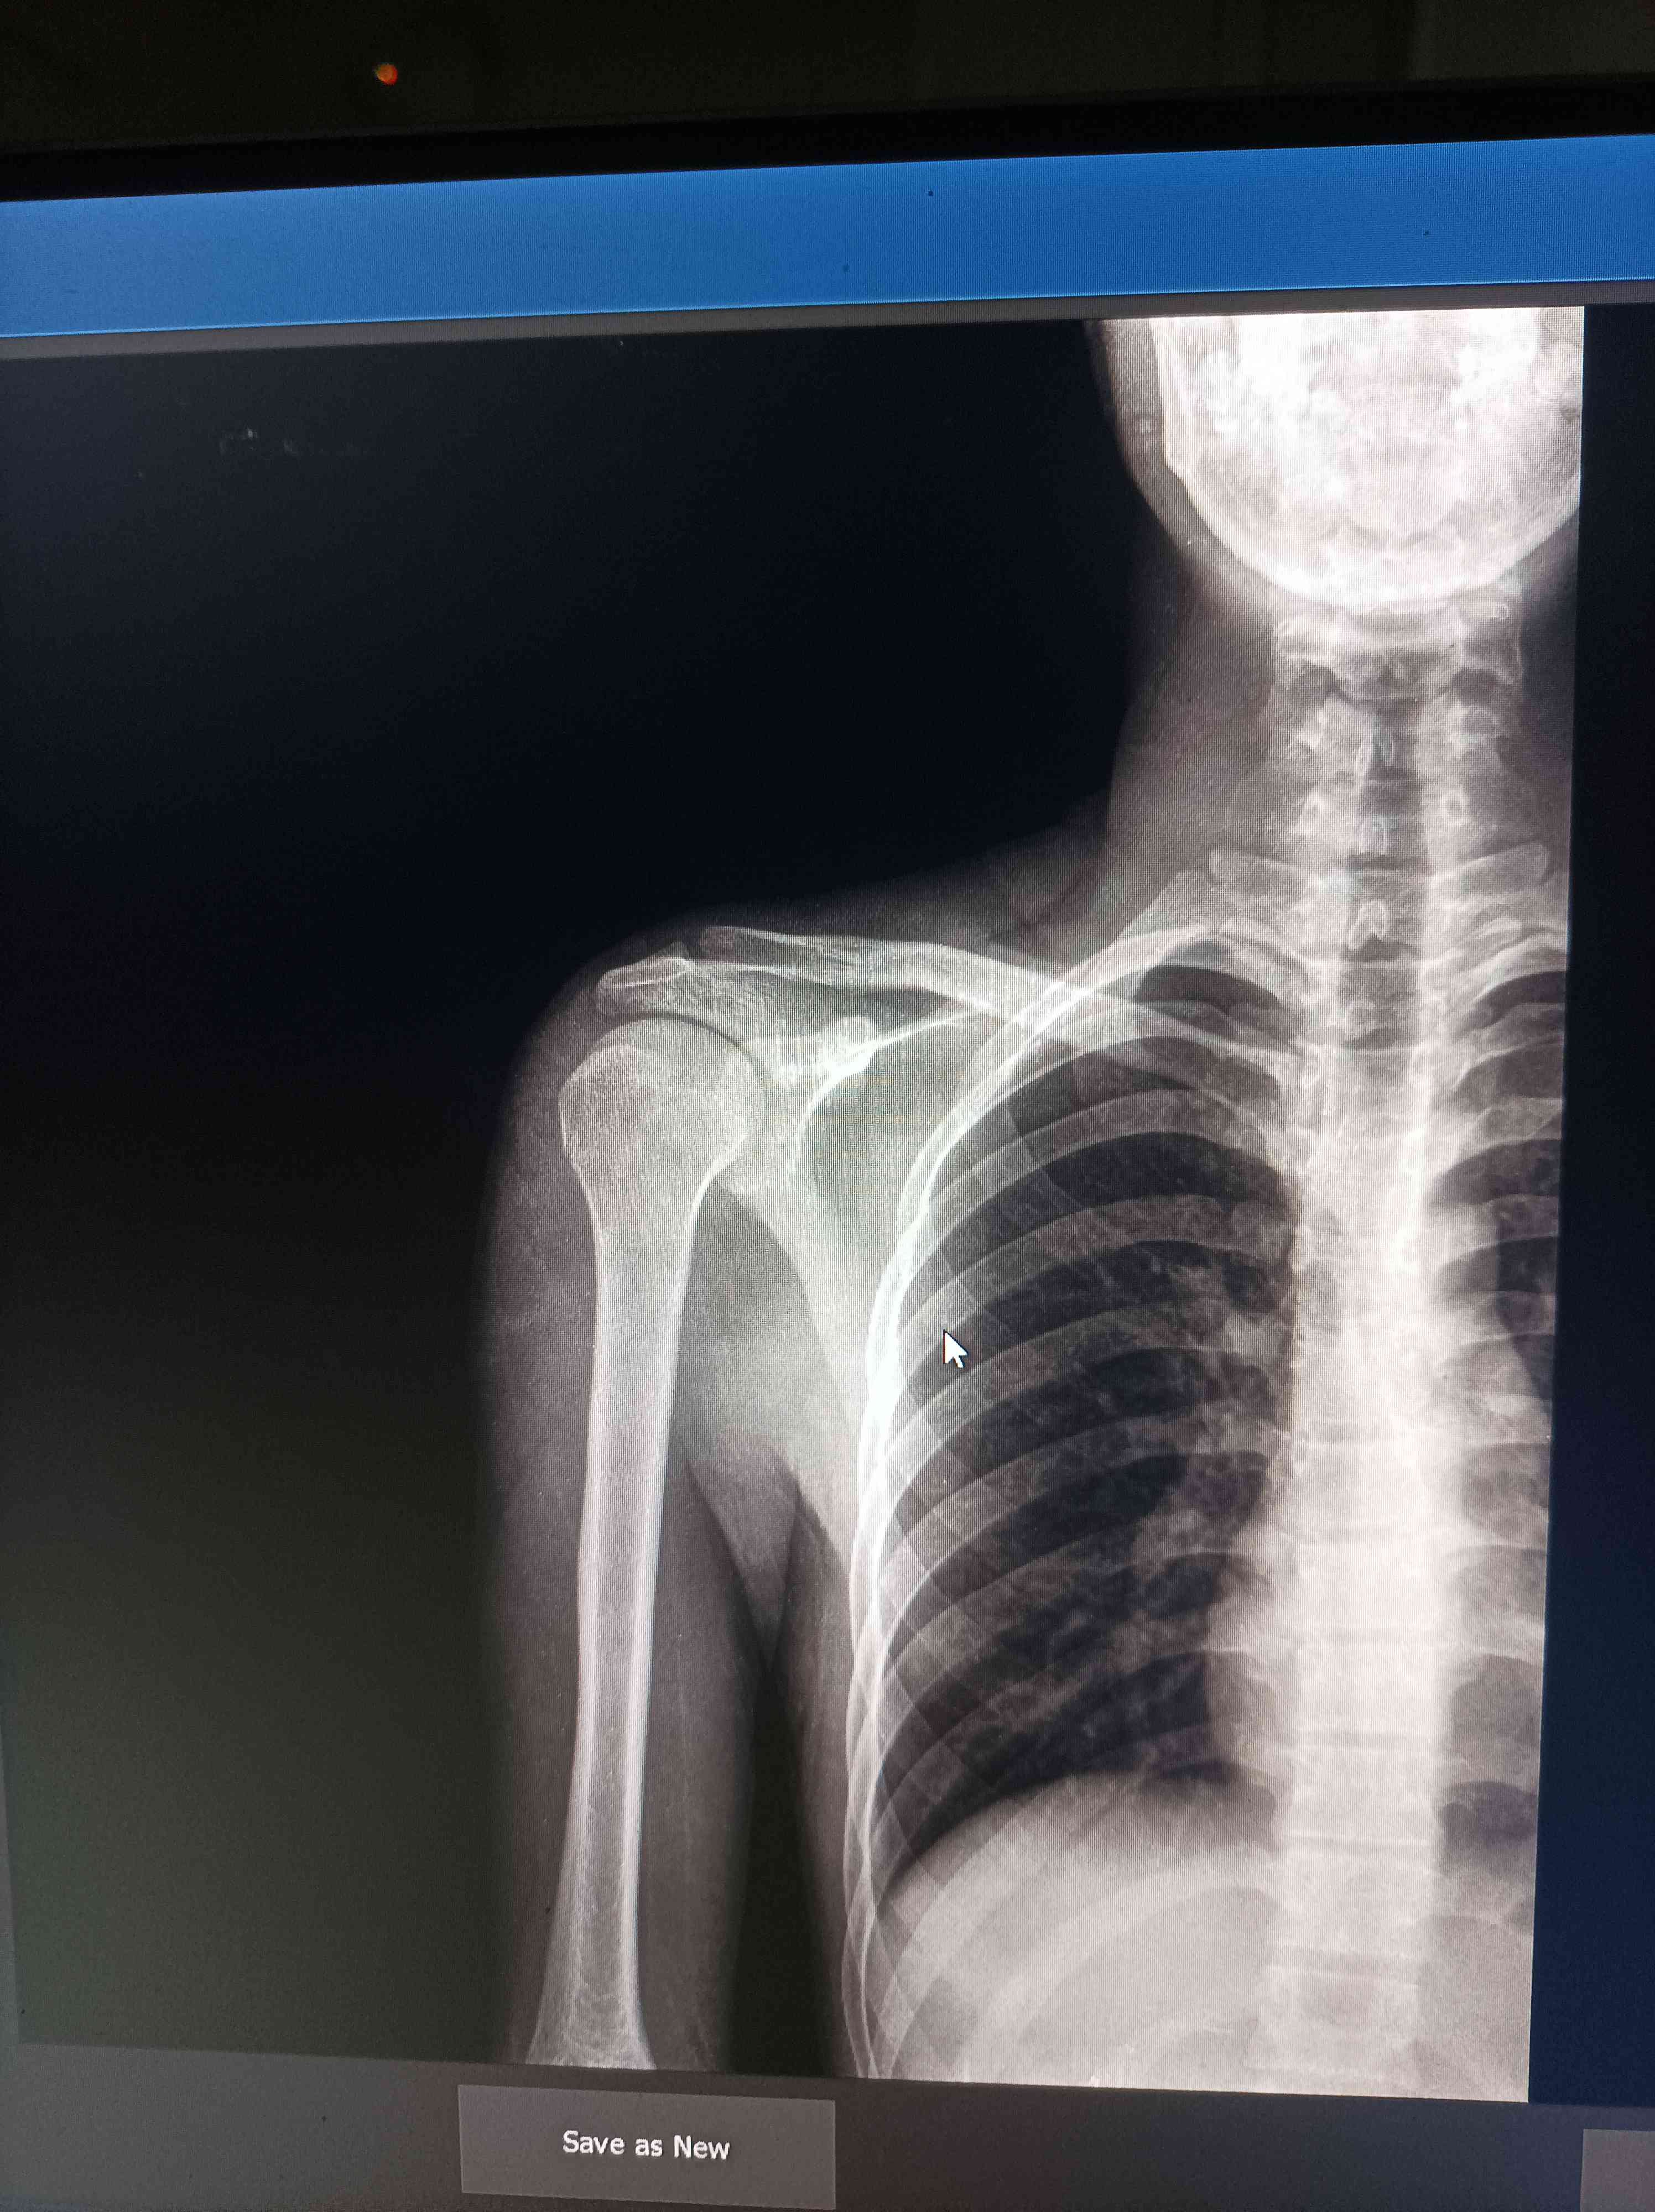

اعاني من الم في منطقة الكتف الموضحة في صورة الاشعة

أعاني من ألم في منطقة الكتف الموضحة في صورة الأشعة المرفقة. أرجو منكم إلقاء نظرة على الصورة وإفادتي بالتشخيص المبدئي وما هي الخطوات أو الحلول المقترحة. شكراً لكم

الصوره لا تكفي للتشخيص والاسباب كثيره ومتنوعه ممكن موضعي او روماتزمي مشاكل الاوتار ممكن الرقيه الخ لذا مهم مراجعة طبيب روماتيزم لاجراء اللازم او لتوجيهك للتخصص المعني 0 2025-12-27T08:36:42+00:00 2025-12-27T08:36:42+00:00